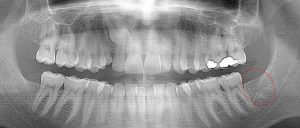

This 8 year old patient has 4 permanent 1st “6 year” molars fully erupted (circled). All 4 permanent 2nd molars are deep in the jaw on both arches and are just starting root formation (circled). There are no 3rd molar tooth buds evident below, but natural 3rd molar agenesis that occurs 7% of the time cannot be confirmed until age 14.

This 21 year old patient has all four 3rd molars present (circled). The roots are approximately 2/3rds formed. The lower right 3rd molar cannot erupt any further; it is distally tipped into the ramus of the mandible. The lower left 3rd molar likely will not erupt any further; it is pushing into the undercut of the distal of the 2nd molar.